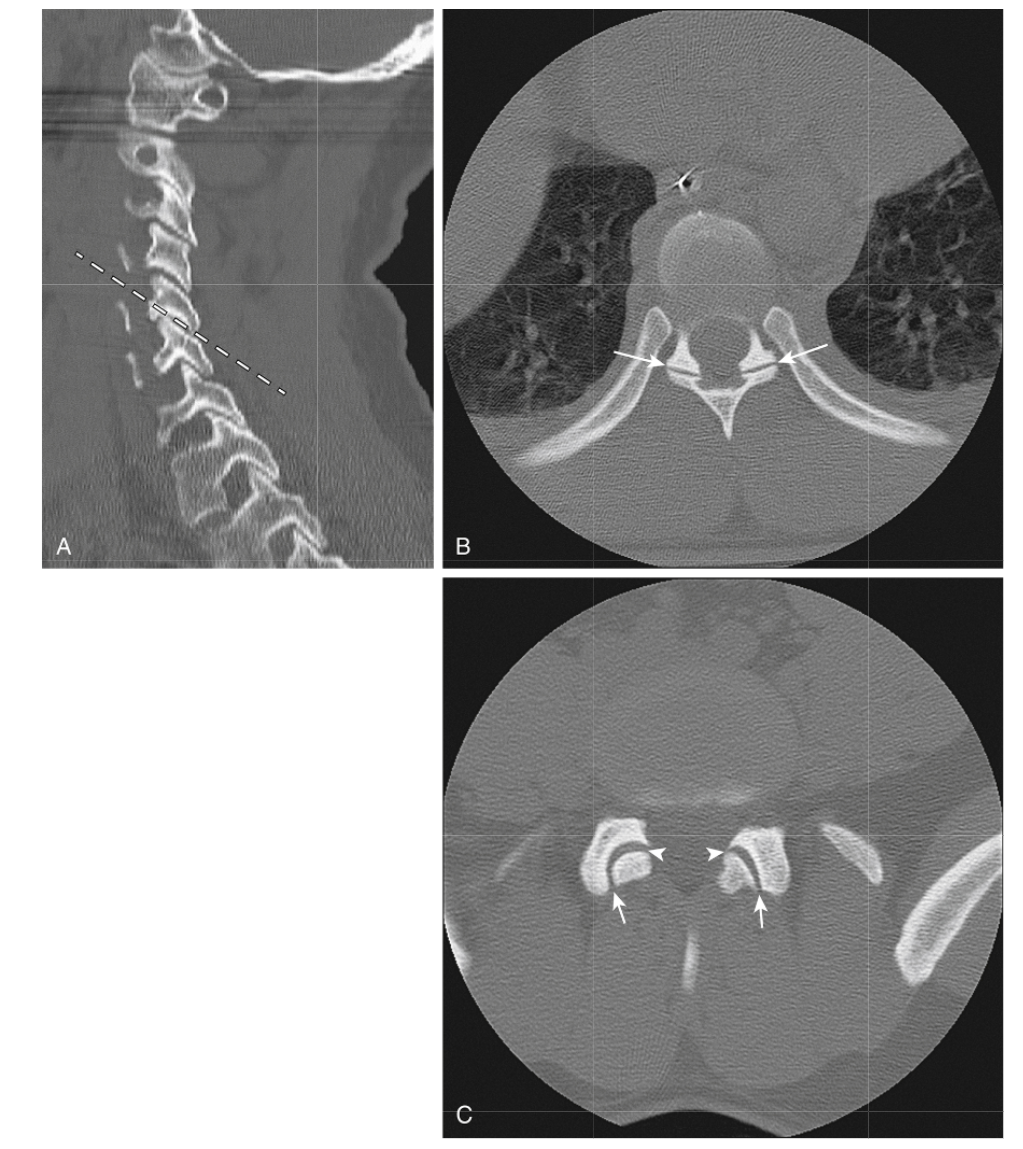

How are cervical, thoracic, and lumbar facet joints oriented?

Cervical - obliquely from superior to posterior withh ventral to dorsal angle

Thoracic- Angled in coronal plane (limits access)

Lumbar- Posterior is oblique in sagittal plane, and anterior is in coronal plane